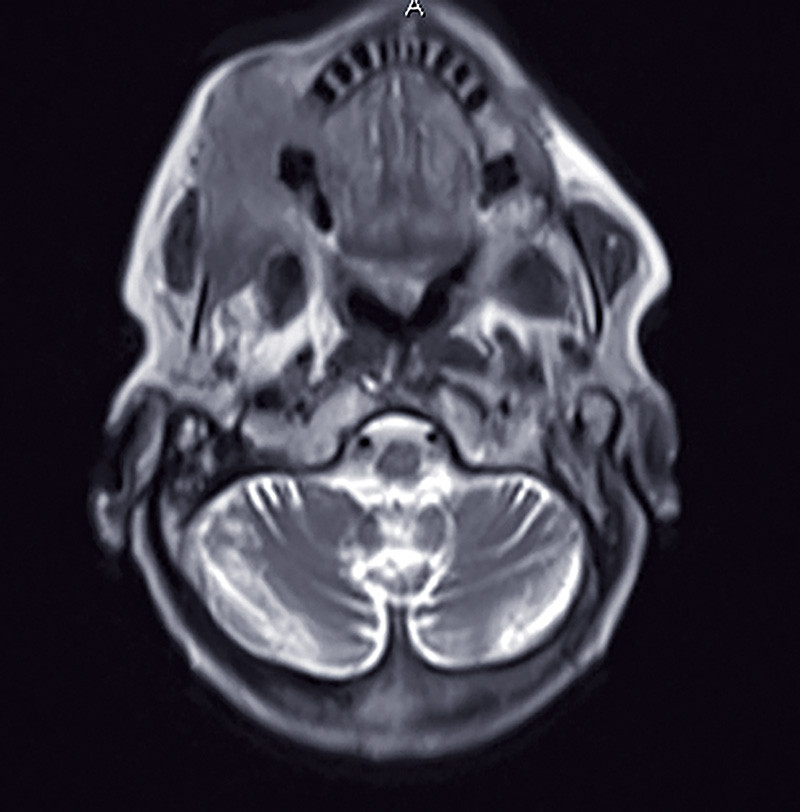

c. Examen IRM